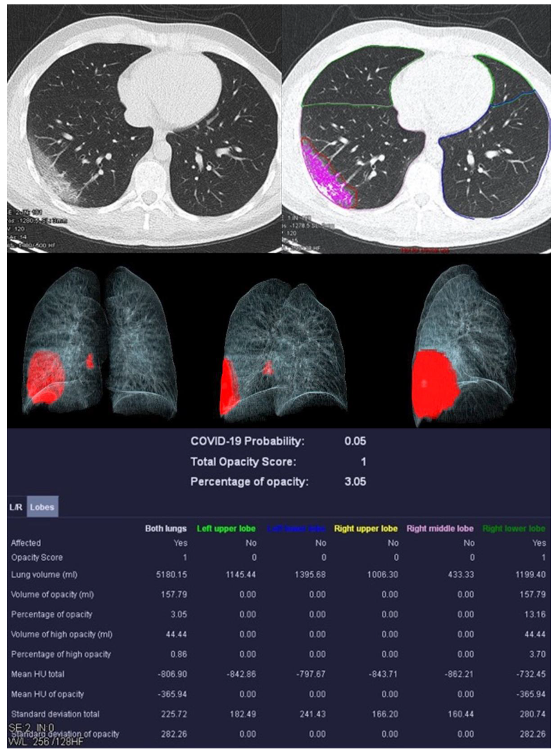

3.2. Image Analysis

| Mean COVID-19 Probability ± SD | 0.80 ± 0.36 | 0.33 ± 0.4 | 0.55 ± 0.47 | 0.66 ± 0.44 |

| Mean LSS ± SD | 8 ± 5 | 5 ± 4 | 5 ± 6 | 0 ± 0 |

| Mean PO ± SD in % | 26.39 ± 23.22 | 12.52 ± 17.97 | 18.90 ± 26.27 | 0.05 ± 0.12 |

| Mean PHO ± SD in % | 6.42 ± 7.68 | 3.60 ± 4.47 | 5.86 ± 10.04 | 0.01 ± 0.02 |